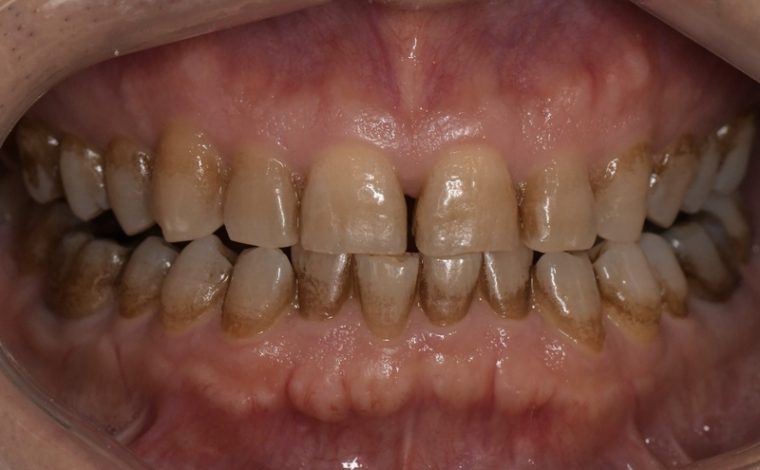

CASE 3

Before

After

基本情報

| 年齢・性別 | 30代・女性 |

| 主訴 | 定期検診 |

| 治療内容 | PMTC |

| 治療期間 | 60分 |

| 治療費 | 5,750円 |

| リスク・副作用 | しみる可能性があります。 |

| 治療方針 | PMTCでステインの除去。 |

| 担当者所見 | ステインが付きやすいため、3カ月毎の定期検診で除去する。 |